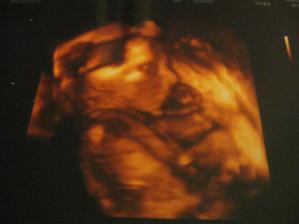

2. 3. 2011 Dneska jsme se byli vyfotit ve 3D 🙂 Chtěli jsme i video ale Kačenka měla půlnoc tak nebylo co točit 🙂